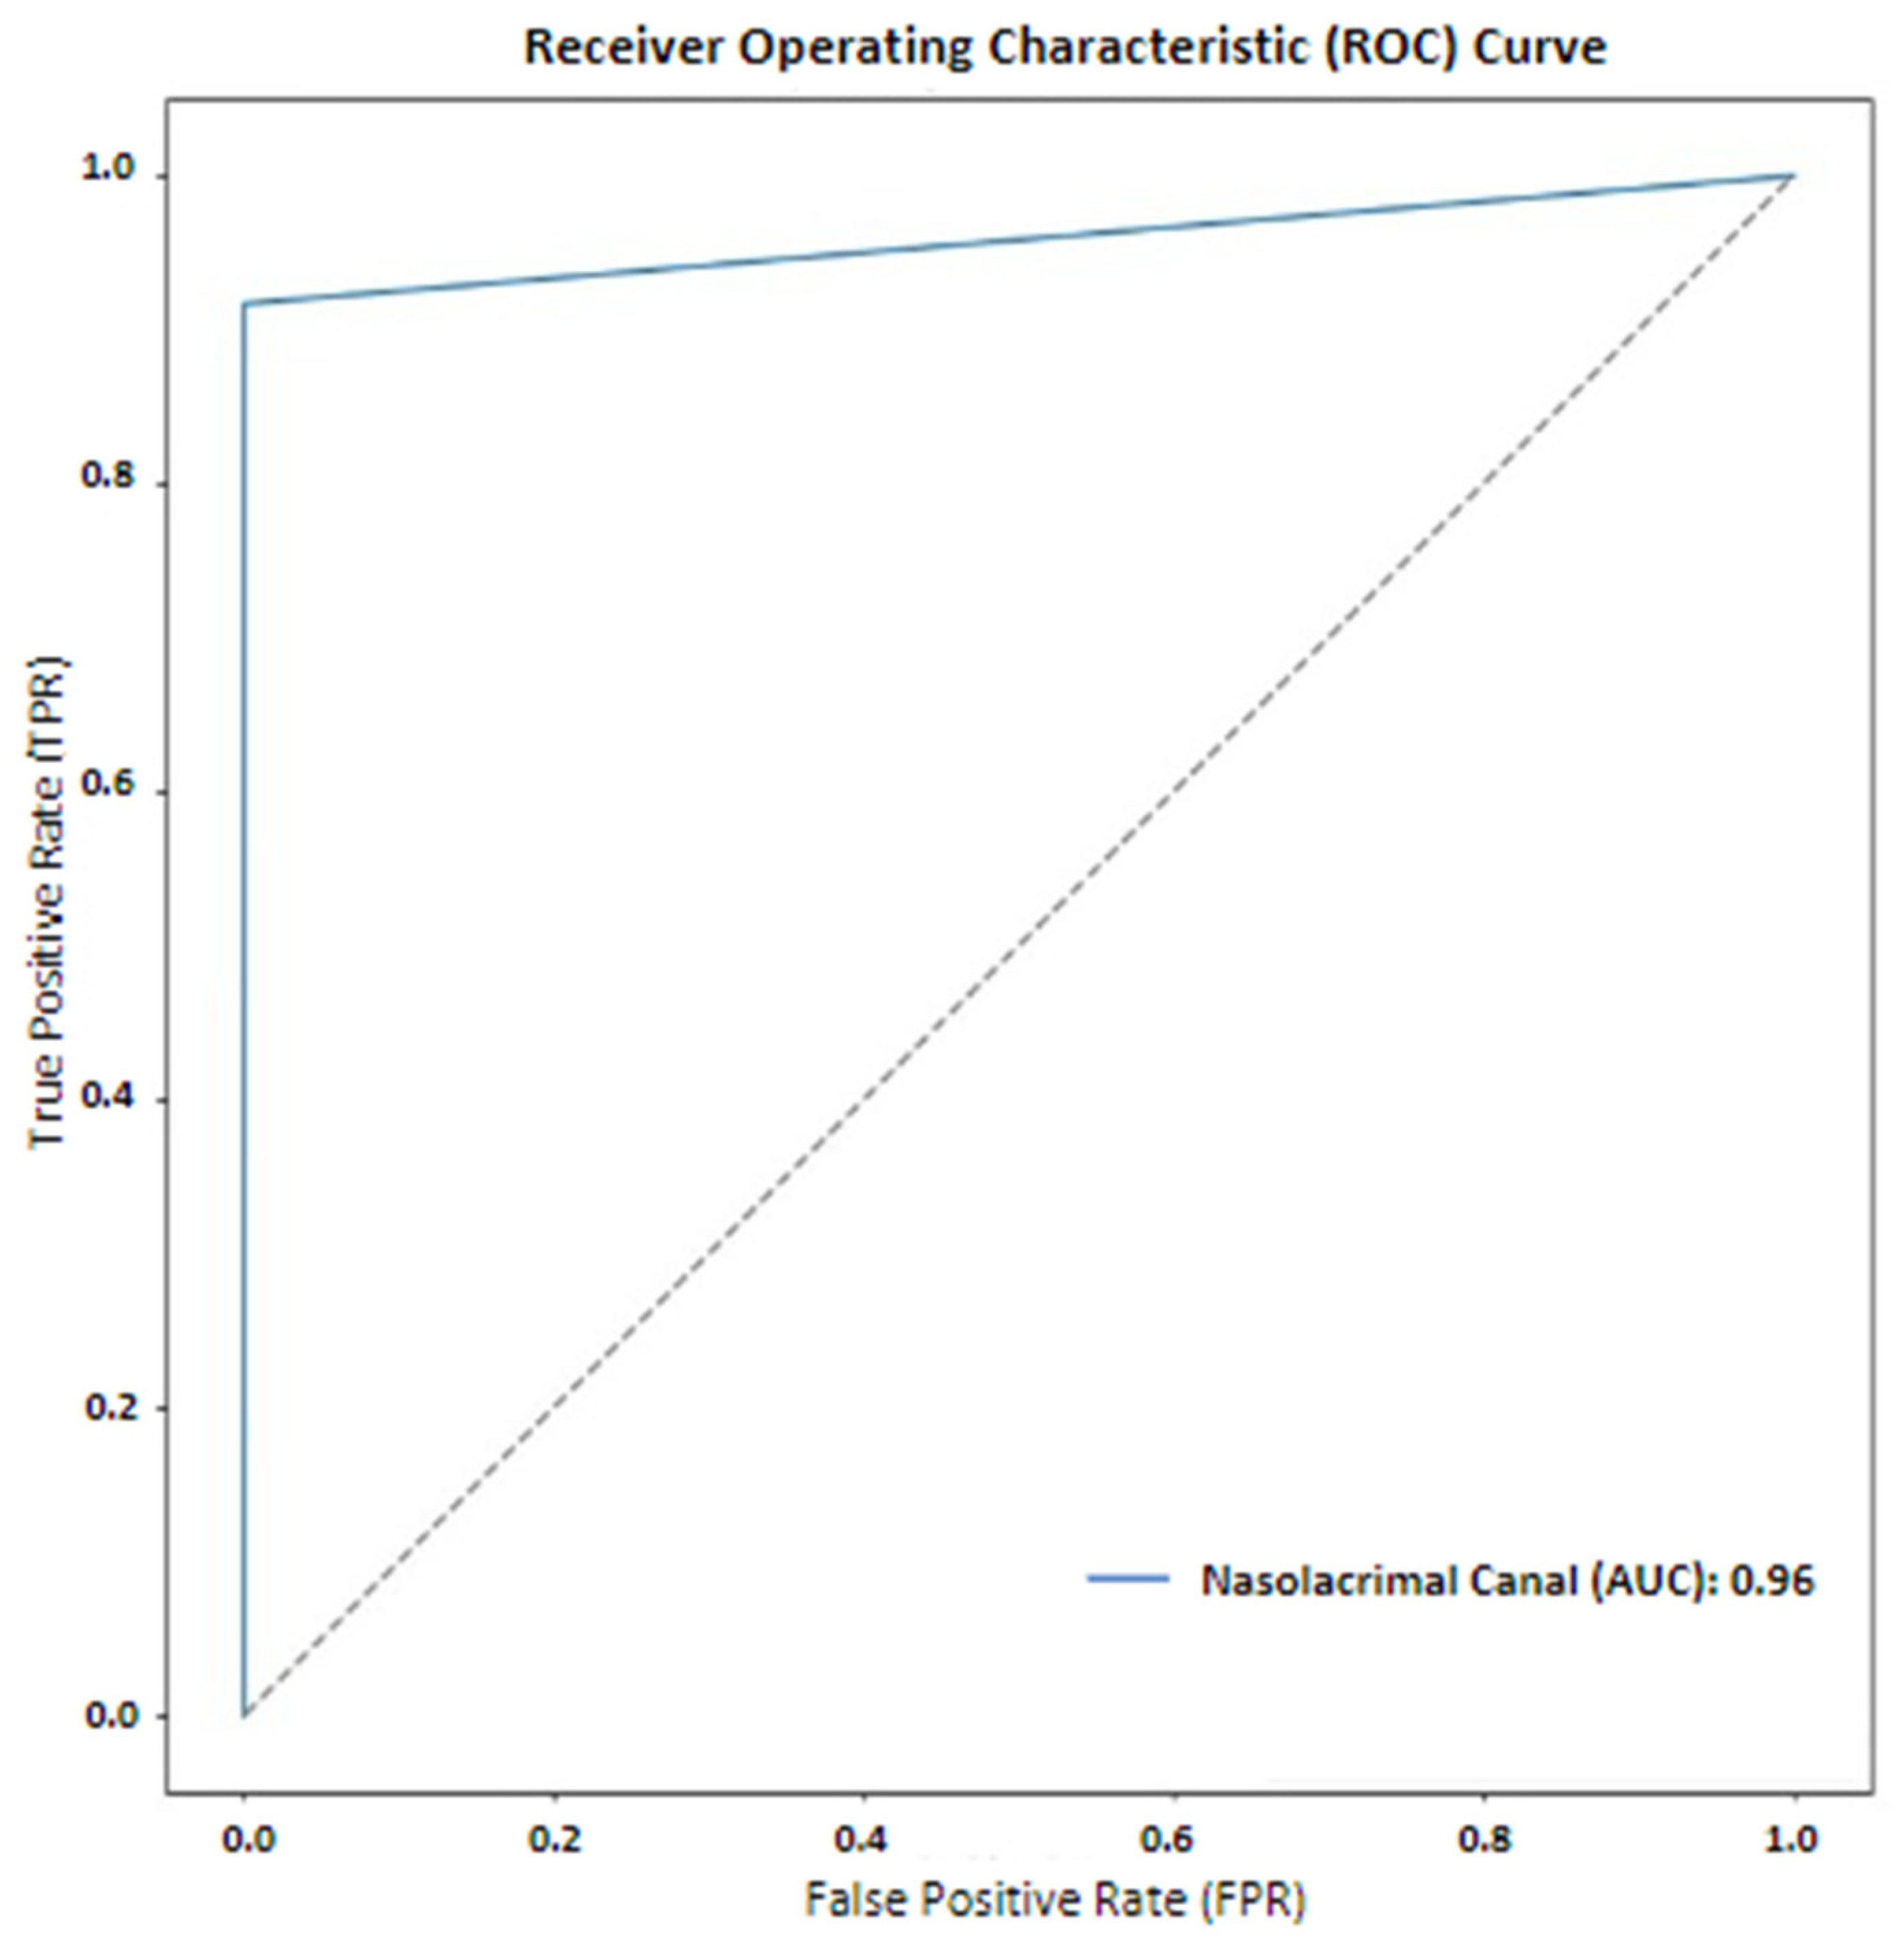

3. Results